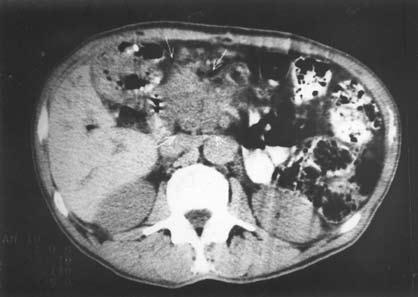

Компьютерная томография (КТ) является рентгенологическим методом высокой разрешающей способности, достаточно широко используемым при исследовании ПЖ. В принципе метод позволяет получить данные, аналогичные УЗИ, однако в ряде случаев дает возможность уточнить последние, например, при ожирении больного, наличии метеоризма, преимущественной локализации изменений в области хвоста железы (рис. 140).

Рис. 140. КТ при хроническом кальцифицирующем панкреатите. На снимке видны кисты головки ПЖ, расширенный ГПП и кальцинат в его просвете.